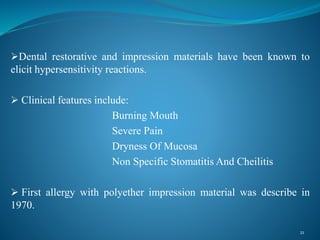

Clinical Characteristics Of An Allergic Reaction To A Polyether Denta…

www.slideshare.net

www.slideshare.net

allergic reaction impression polyether clinical

Clinical characteristics of an allergic reaction to a polyether dental. Clinical characteristics of an allergic reaction to a polyether dental. Clinical characteristics of an allergic reaction to a polyether dental